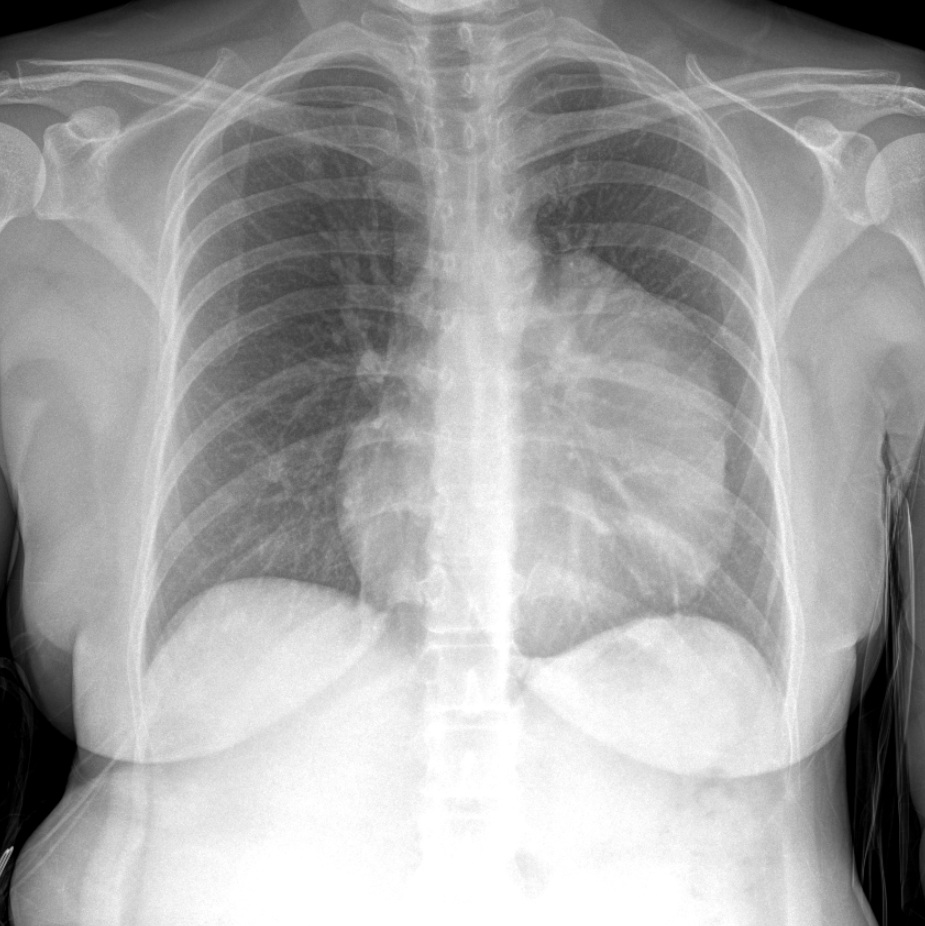

Chest X-ray fundamentals

5 cases · video teaching · quiz

Pulmonary consolidation & pneumonia